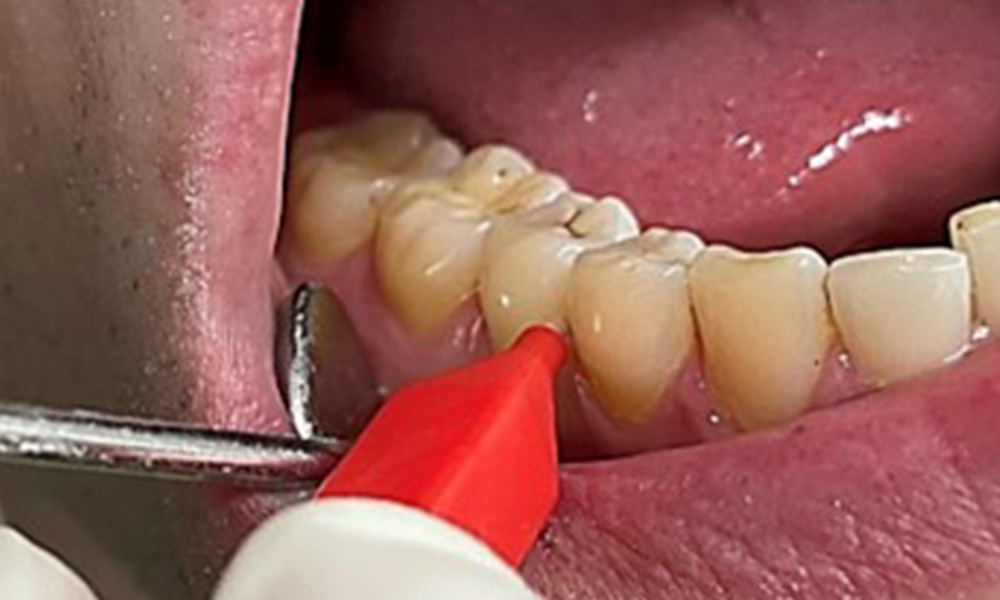

Instruktion & Motivation sind wichtige Bestandteile in der Sitzung. Gutes

häusliches Mundhygieneverhalten und – verständnis sind dem Patienten wichtig. Es zeigen sich insbesondere an den ZahnhalsbereichenPlaqueakkumulationen (Abb. 8).

Plaqueakkumulationen im Zervikalbereich

Abb. 8: Die Pfeile markieren Plaqueakkumulationen im Zervikalbereich, © Dr. R. Krapf

Diese sind mit dem Patienten zu besprechen und Verbesserungen in der Zahnputztechnik zu üben. Gerade aufgrund der Erosionen und Attritionen ist ein weicher Zahnbürstenaufsatz für die häusliche Mundhygiene anzuraten.